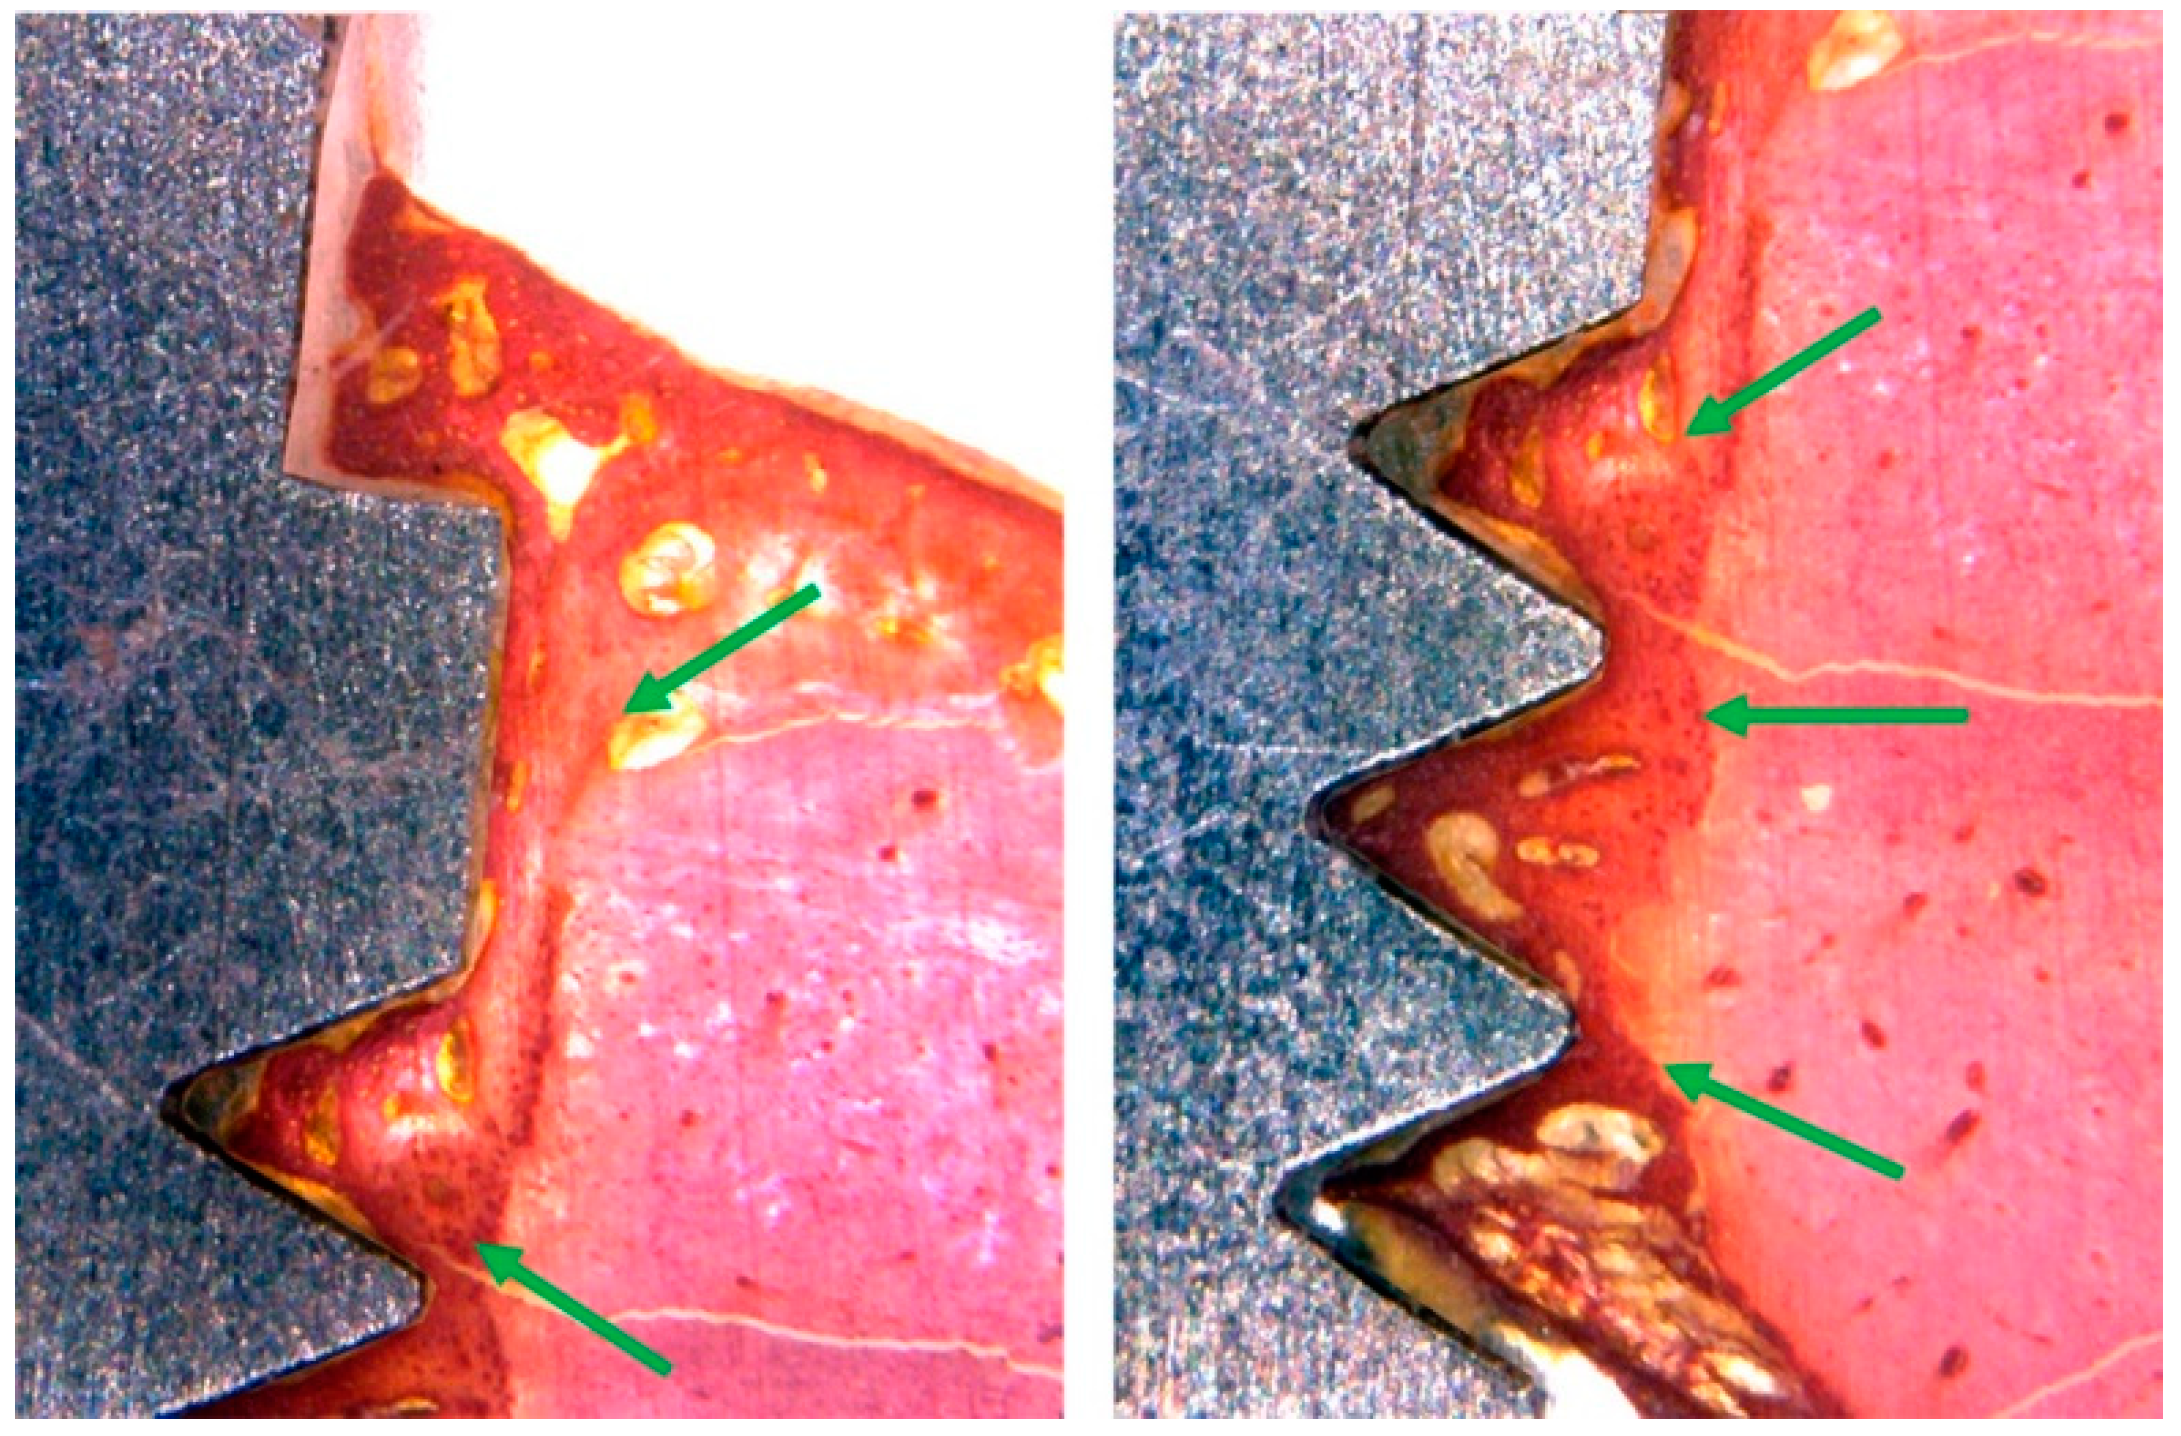

3.3. Histomorphological Analysis